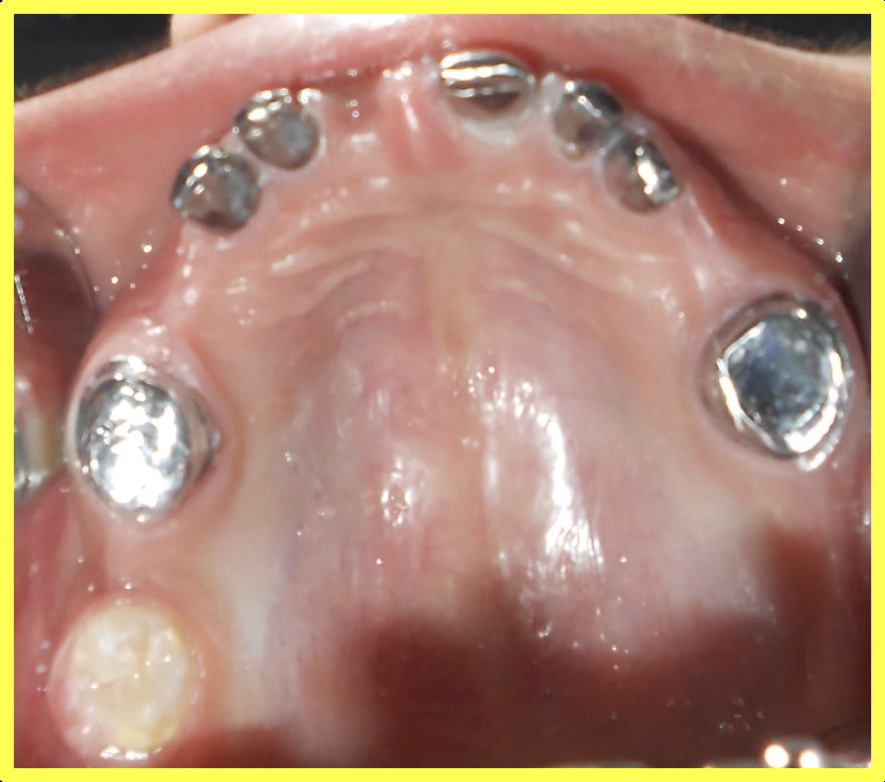

Endodontic treatment performed on all remaining deciduous teeth to ensure they could serve as stable abutments for telescopic prosthesis.

Custom telescopic copings were designed and fabricated to fit over prepared teeth, providing retention and support for the removable prosthesis.